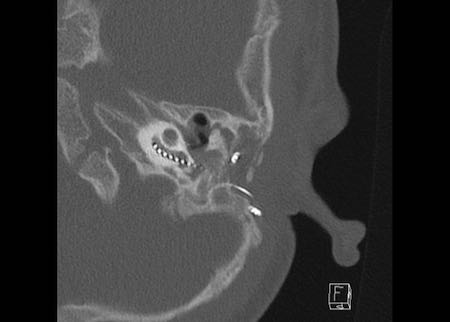

Ca lâm sàng 2

Các hình ảnh này cho thấy một điện cực cấy ghép bị lạc chỗ.

Điện cực ốc tai được đưa vào phía dưới vòng đáy của ốc tai và kết thúc ở vùng hạch gối (geniculate ganglion).